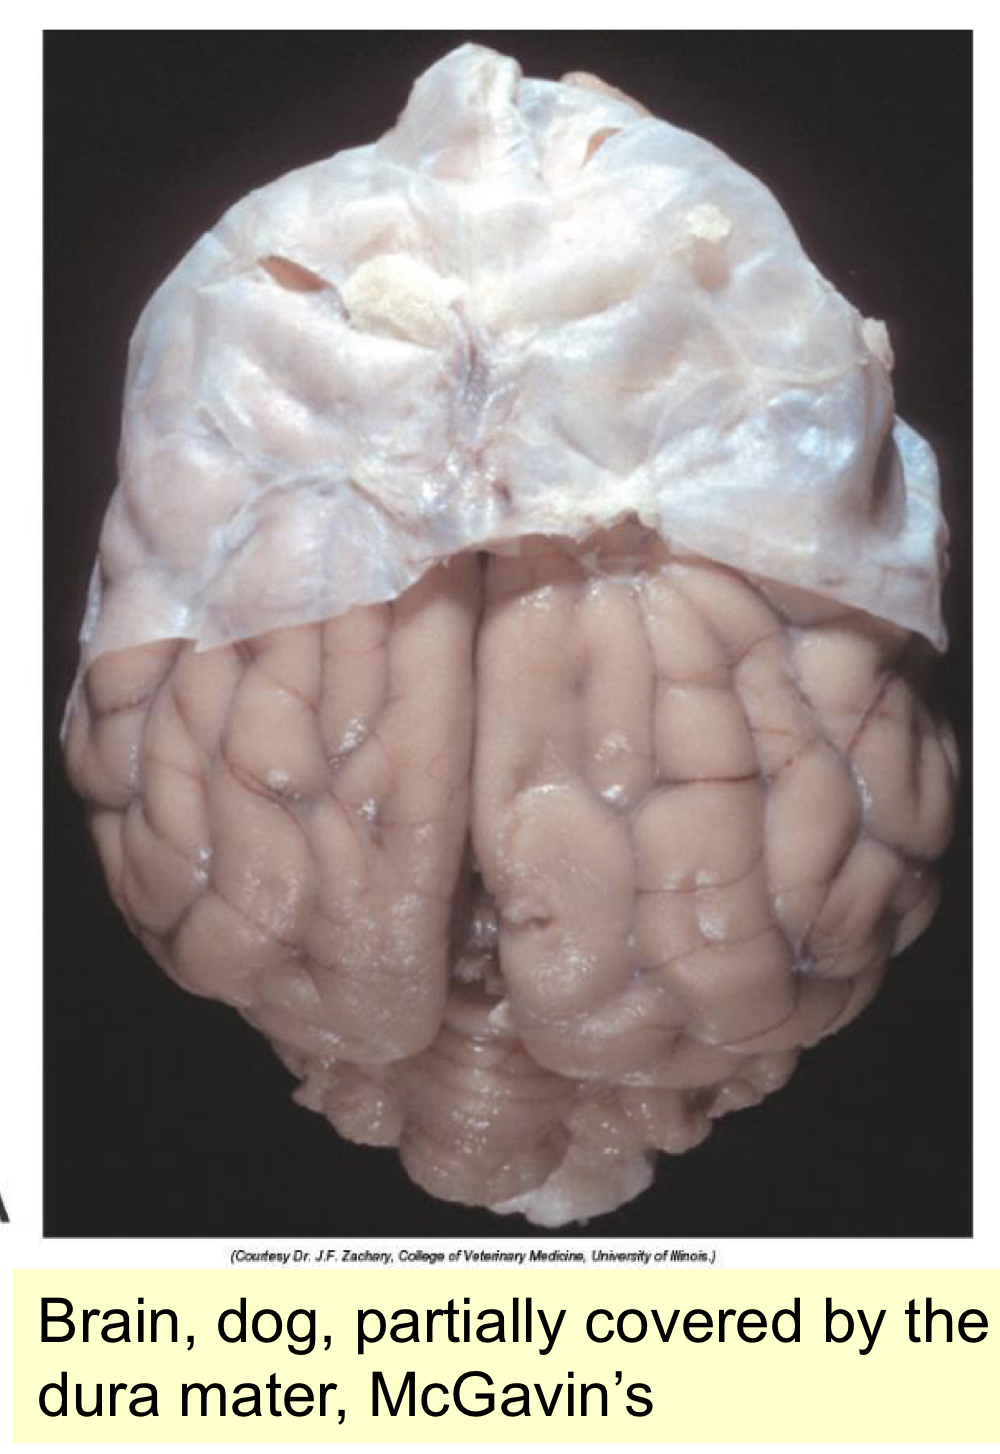

What are the layers of the meninges?

A

1. dura matter - connective tissue adhered to the skull endosteum

2. arachnoid space - allows the movement of CSF from ventricles and spinal cord

3. pia matter - parenchyma of the brain